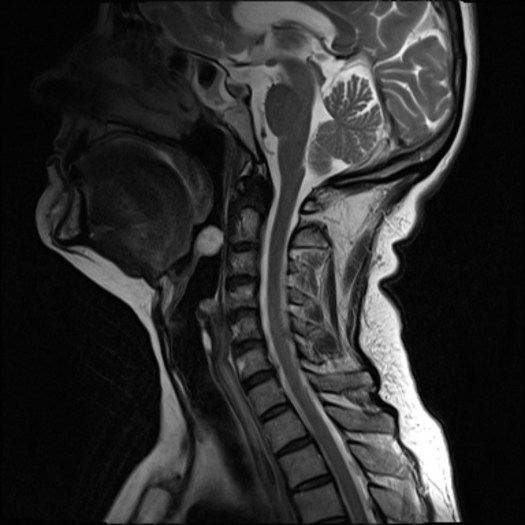

Abscess of the Anterior Belly of the Digastric

https://pubmed.ncbi.nlm.nih.gov/31232606/

Abscesses within muscles in the Head and Neck are exceptionally rare, others having been described by Luc, Bezold, and Citelli. Mr Pankhania describes the first ever case of this variety under the tongue in the anterior digastric muscle.